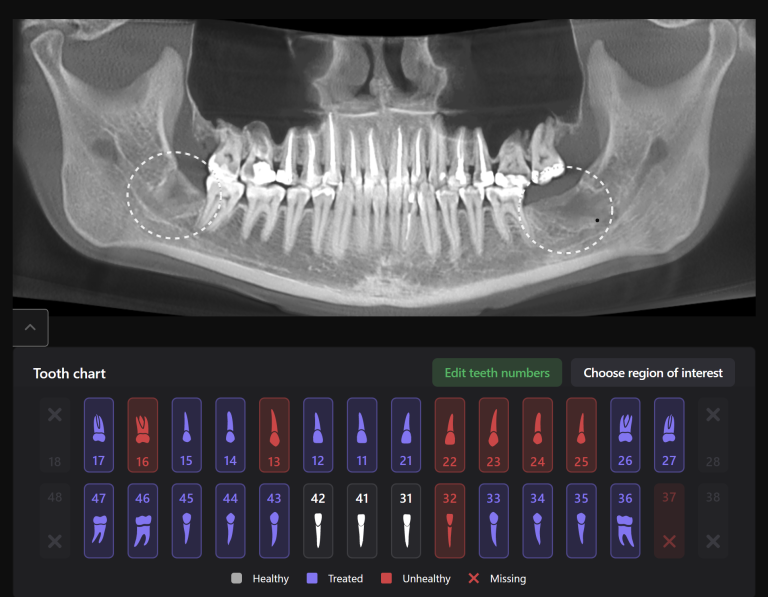

Diagnocat assists clinicians in implant treatment planning, both in guided surgery and in a classical approach. Let’s explore the capabilities of Diagnocat through a clinical case example of planning implant treatment for the replacement of missing teeth 17,16 (Universal 2,3)